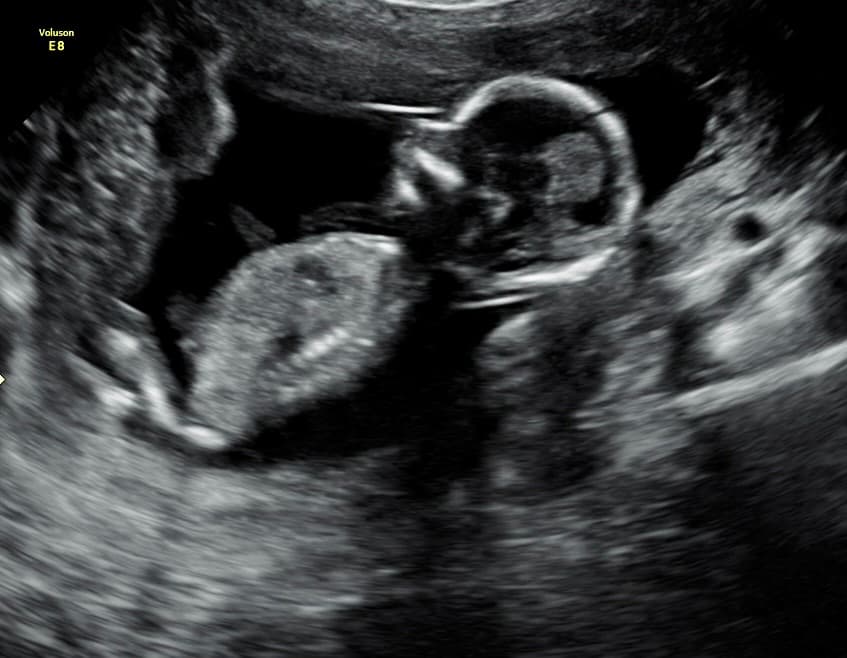

Book NowTahlequah's first 3D/4D ultrasound studio

At Magnolia Fetal Imaging, we provide a warm, relaxing environment where you can bond with your baby through advanced 3D/4D & HD ultrasound technology. Our studio focuses on capturing precious keepsake moments for families — gender reveals, early looks, and high‑definition images you will cherish for a lifetime.

All sessions are non‑diagnostic and designed purely for bonding and keepsake entertainment.